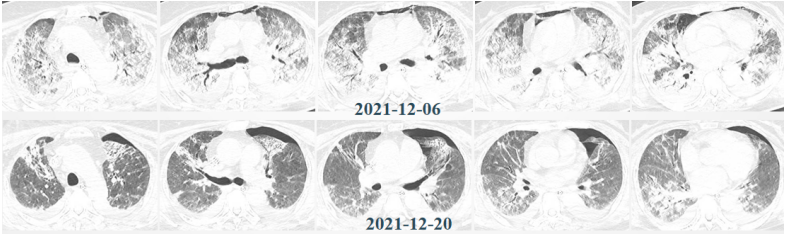

患者,女,50岁;活动后喘息20天,加重伴发热3天,2021年11月19日转入我院。入院胸部CT显示:双肺实变,磨玻璃影(图1)。11月24日复查胸部CT可见病变进展迅速(图2)。予患者气管插管机械通气、俯卧位等,呼吸衰竭未见改善。遂于11月25日启动VV-ECMO(转速2860 rpm,流量4.5 L/min,氧浓度100%)。追问病史:患者入院前1月有活动后气促症状,自觉全身不适,近2年有眼干、口干不适。进一步检查发现,ANA反应阳性(+),ANA核型为胞浆颗粒型(异常);抗SSA/Ro抗体阳性(++)、抗Ro-52抗体阳性(+++)。诊断:急性间质性肺炎(AIP);Ⅰ型呼吸衰竭;混合性结缔组织病。治疗:VV-ECMO+呼吸机辅助通气+俯卧位通气、激素(甲强龙80 mg×7天,60 mg×3天,40 mg qd)、免疫抑制剂(环磷酰胺400 mg qd×3天)、抗感染(哌拉西林他唑巴坦4.5 g q12h+莫西沙星0.4 g qd+氟康唑氯化钠注射液20 mg qd)、抗凝等。在随后的一段时间内,患者影像学改善不明显(图3)。直至12月20日,复查胸部CT可见患者肺部病变较前明显吸收(图4)。2021年12月31日VV-ECMO撤机后,继续气切呼吸机辅助通气,甲强龙40 mg qd抗炎治疗,继续抗感染治疗,2022年1月7日脱机,1月21日气管封管,1月26日出院。后续治疗:强的松25 mg qd,环磷酰胺600 mg q2w×4次,序贯吗替麦考酚酯0.5 g bid。重症间质性肺疾病(ILD)在诊断方面需要考虑以下问题:是ILD吗?是哪种ILD?严重程度如何?在治疗方面,除了生命支持(呼吸支持重点)和病因治疗,并发症的处理也至关重要。重症ILD的诊断包括两方面,一方面是通过影像学、病史+临床表现、BALF-NGS、实验室检查、肺活检等对ILD进行诊断;另一方面涉及重症,患者多面临呼吸衰竭甚至多器官衰竭,因此时间更加紧迫。在ICU内最常见的重症ILD包括:特发性肺纤维化急性加重(AE-IPF)、自身免疫相关性ILD、肿瘤治疗相关性ILD、隐源性机化性肺炎(COP)、AIP、过敏性肺炎(HP)、急性嗜酸性粒细胞性肺炎(AEP)、药物相关ILD等。在影像学方面,最易导致重症的类型有弥漫性磨玻璃影和实变影。最常见的鉴别诊断就是重症肺部感染。表现为弥漫性磨玻璃影或实变影的ILD较为多见,例如:HP、嗜酸性粒细胞性肺炎(EP)、结缔组织病相关间质性肺病(CTD-ILD)、非特异性间质性肺炎(NSIP)、脱屑性间质性肺炎(DIP)、淋巴细胞性间质性肺炎(LIP)、机化性肺炎(OP)、AE-IPF、肺泡蛋白沉积症(PAP)、肺泡微结石症、结节病、弥漫性肺泡出血综合征、肺水肿等。而很多感染性疾病影像学也可表现为磨玻璃影,例如:卡氏肺孢子菌肺炎(PCP)、病毒性肺炎、巨细胞病毒性肺炎、支原体肺炎。尽管如此,ILD也有部分影像学具有特征性,可以被识别。图5左表现为肺陷闭,也称为“猪头肉冻征”,这是典型的亚急性HP的影像学特征。图5右表现为弥漫性磨玻璃影,但以肺门向外扩展,外面有肺大泡,这是典型的PCP表现。临床上多见自身免疫性疾病导致的ILD,此类疾病也具有共同的特征,例如双肺弥漫,病理方面以NSIP或OP为主要特征。但也有部分患者可以出现弥漫性肺泡损伤(DAD)特征。如图6所示,左图为ANCA相关性血管炎,右图为MDA5相关性间质性肺病。因此,一定要警惕容易发生这种病理改变的自身免疫性疾病。